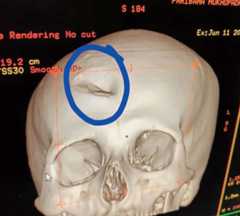

A dent (circled) is seen in a CT scan image

A dent (circled) is seen in a CT scan imageDoctors who circulated it on social media said the image shows the skull of Paribaha

Two junior doctors at NRS, Paribaha Mukhopadhyay and Yash Tekwani, suffered head injuries and have been hospitalised. Mukhopadhyay, who suffered a skull fracture, has undergone surgery at the Institute of Neurosciences in Mullickbazar. Tekwani is admitted to NRS.